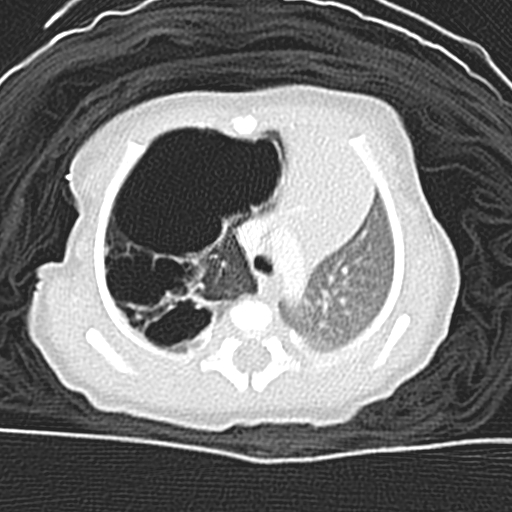

La polidramnia se puede identificar mediante la realización de un ultrasonido por parte del médico. Sin embargo, la mujer puede presentar algunos signos y síntomas que pueden indicar la presencia de polidramnia, como desconforto abdominal, dificultad para respirar, piel lisa y brillante en la región abdominal, e hinchazón en la región inferior del abdomen. Durante el examen físico, el médico puede tener dificultad para palpar al feto y auscultar los latidos cardíacos fetales.